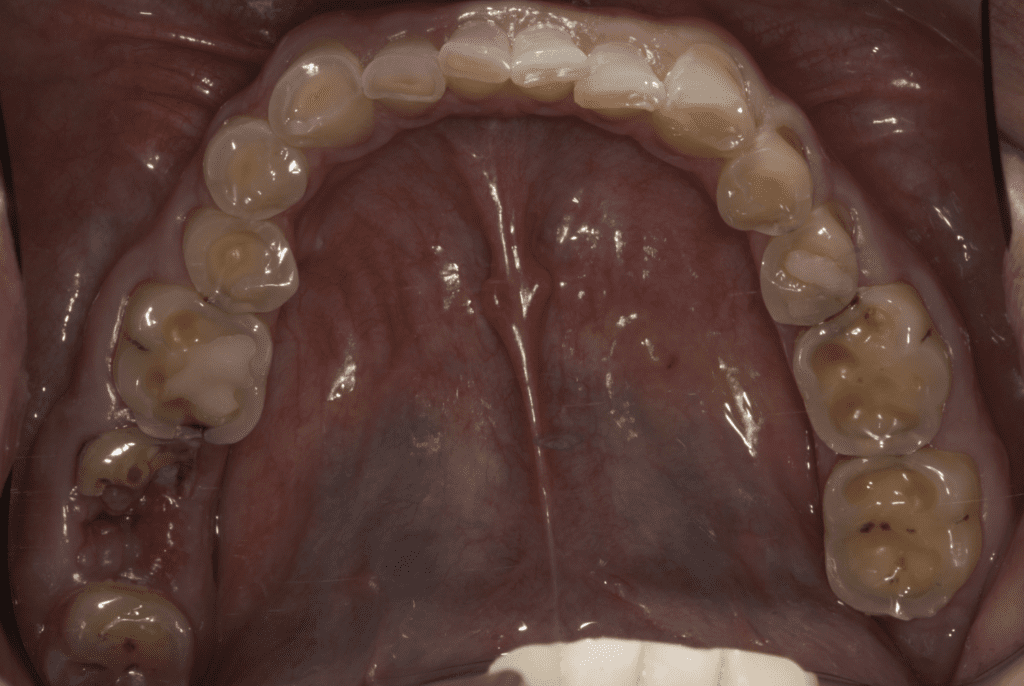

Un signo de erosión dental es la pérdida de la superficie del diente, lo que da lugar a una apariencia lisa y brillante. También puede hacer que los dientes sean sensibles a los alimentos y bebidas calientes, fríos o dulces.

Cuando existe una erosión dental avanzada el esmalte puede desgastarse y descubrir la dentina, las restauraciones pueden comenzar a verse más prominentes si la superficie del diente se disuelve debido a la erosión.

La erosión dental, si no se trata, puede provocar la pérdida progresiva de la superficie del diente. La pérdida de la estructura dental puede requerir un tratamiento dental complejo que incluye restauraciones como carillas, coronas y hasta tratamientos de conducto.